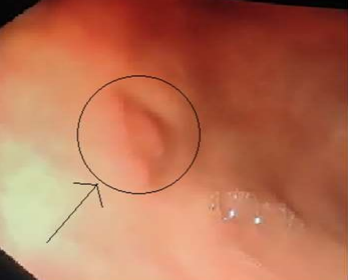

Figure 1-Endoscopic image showing gastric ulcer in fundic region

The endoscopy findings were consistent with presence of ulcer in fundic region (Figure 1) along with presence of well circumscribed circumferential soft,friable and fleshy lesion of approxiametely 1  cm. The bite on bite biopsies were taken from that area and send for analysis. The biopsy report was consistent with caseating granulomas with numerous acid-fast bacilli detected with Ziehl-Neelsen stain and  immunohistochemical analyis for Helicobacter pylori was negative. On subsequent evaluation patient was found to have multiple military nodules on chest X-ray (Figure 2a) and which was confirmed with computed tomography of thorax (Figure 2b).